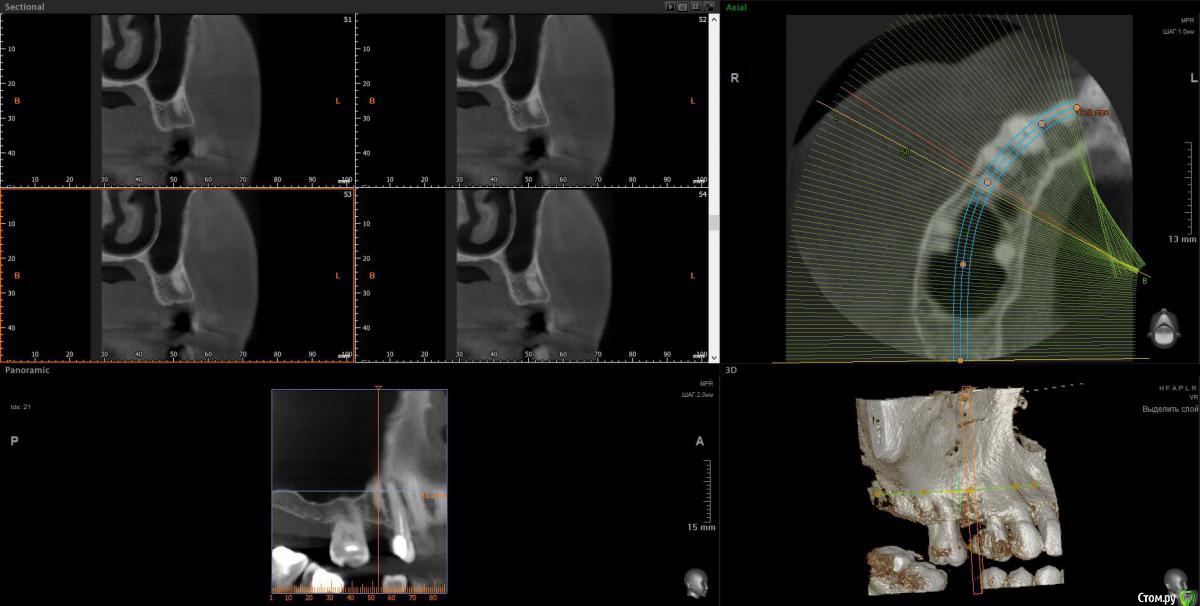

wladdX Опубликовано 11 мая, 2018 Поделиться Опубликовано 11 мая, 2018 Скриншоты зон 15 и 17 Ссылка на комментарий

Elena64 Опубликовано 11 мая, 2018 Автор Поделиться Опубликовано 11 мая, 2018 Скриншоты зон 15 и 1715.jpg15_1.jpg17.jpg17_1.jpgСкажите пожалуйста,а в зоне 7 зуба что не так?Вы отметили крестиками. Ссылка на комментарий

Elena64 Опубликовано 14 мая, 2018 Автор Поделиться Опубликовано 14 мая, 2018 Добрый вечер!Получила сегодня описание из Пикассо : 1.6 зуб. Коронковая часть: восстановлена нерентгеноконтрастной пломбой. Количество корней/каналов: три корня/четыре канала; На дистальной поверхности определяются твердые зубные отложения. В мезиально-щечном корне два канала. Периодонтальное пространство не расширено; Твердая пластинка альвеолы сохранена (Рис.2). В области отсутствующего 1.5 зуба — состояние после удаления. В лунке определяется фрагмент корня с ровным, четким контуром, раз- мерами 3.5х2,4х8,8 мм. Периодонтальное пространство не прослеживается.ДИАГНОСТИЧЕСКОЕ ЗАКЛЮЧЕНИЕ: Частичное отсутствие зубов. Фрагмент корня в лунке отсутствующего 1.5 зуба. Ссылка на комментарий